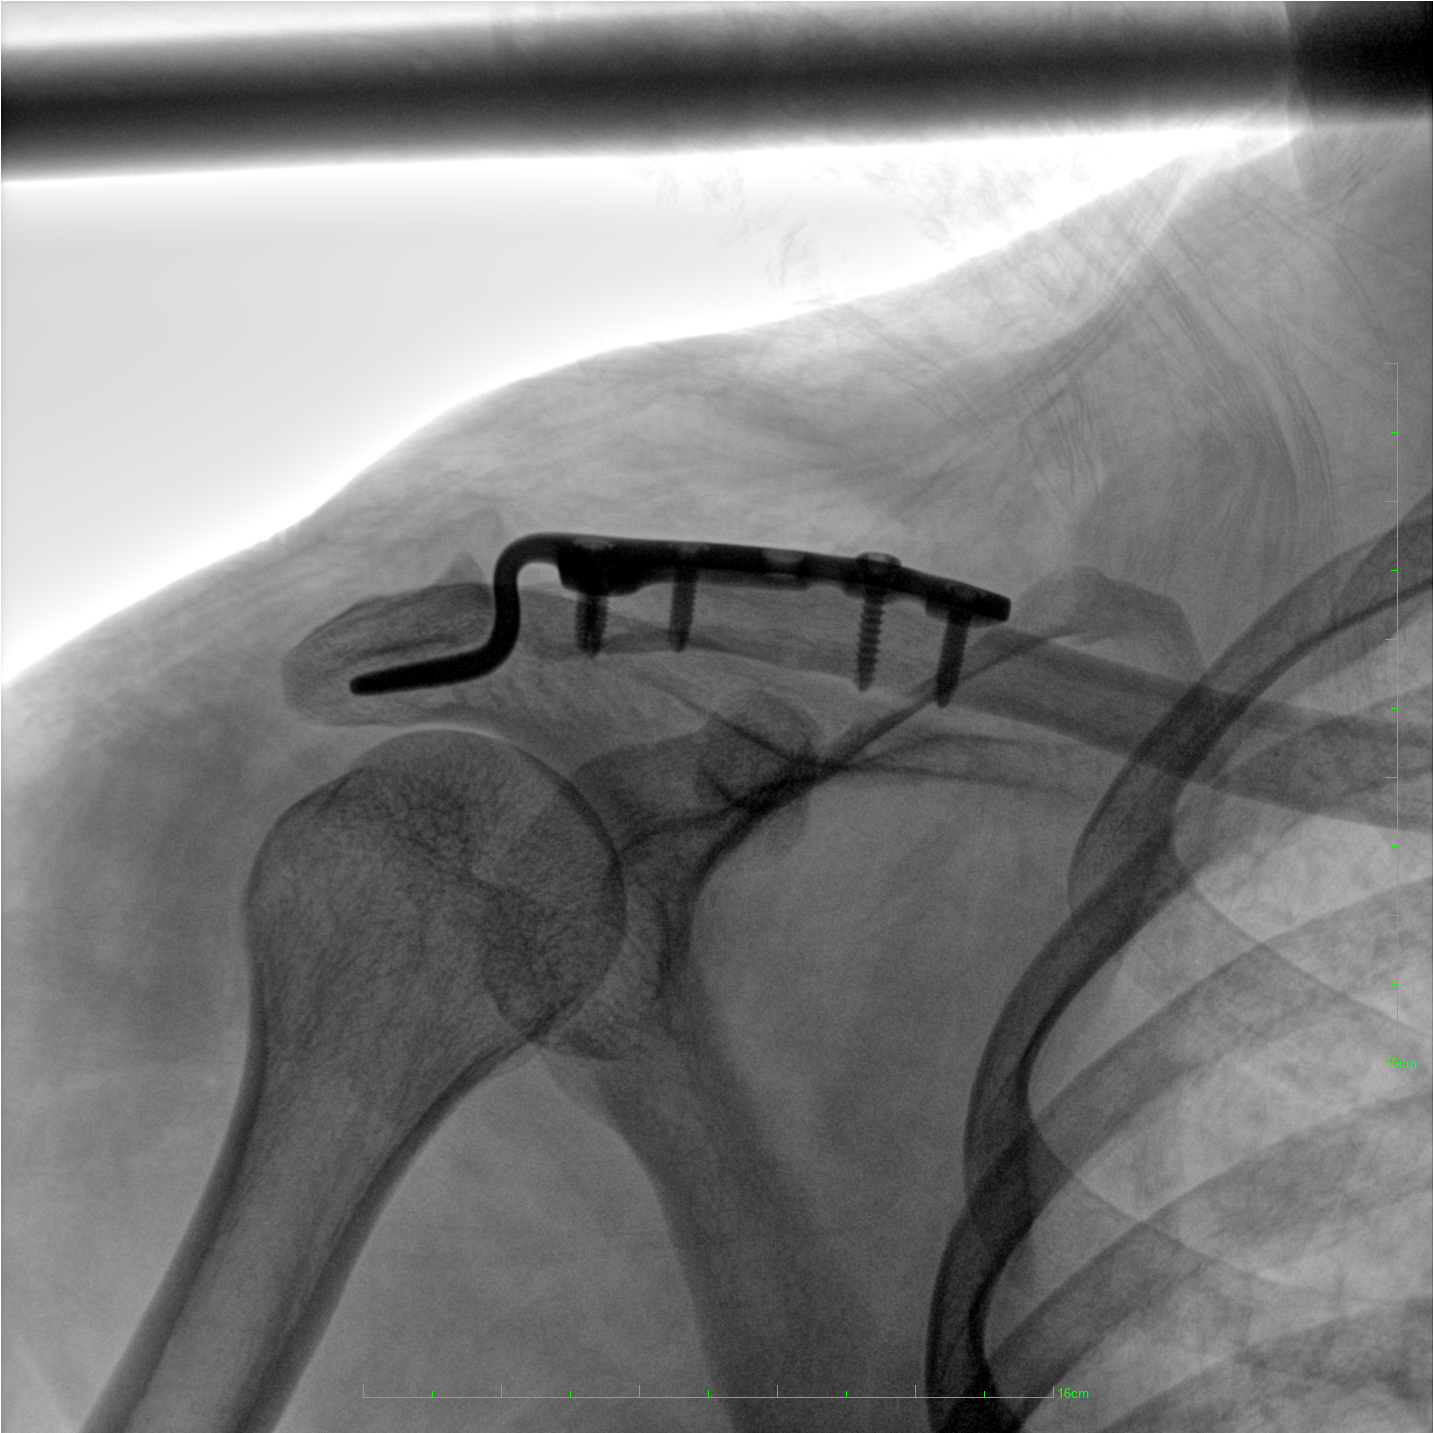

術(shù)中三維成像和橫斷面圖像提供多角度的手術(shù)診斷信息,輔助醫(yī)生進(jìn)行術(shù)中評(píng)估判斷,諸如骨折復(fù)位情況和內(nèi)植入螺釘?shù)某叽绾臀恢?,輔助手術(shù)更好地完成。